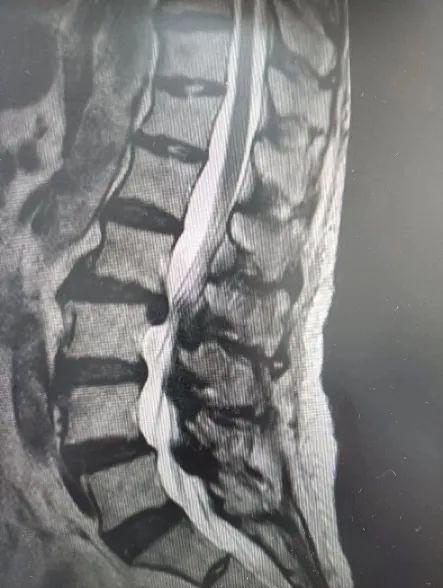

81岁的周阿婆因“左侧腰背痛伴下肢放射痛肢疼痛10年,近3个月加重”。左侧腰腿疼痛整晚辗转反侧,严重影响了生活质量。并且曾在多家医院保守治疗无明显效果,症状反复,不能缓解。于是到杨浦区中医医院骨伤科就诊。

骨伤科将这名患者收入院后,仔细为其查体并完善相关检查,经综合评估,决定联合介入科,为这名患者实施最新诊疗方法——椎间盘切吸术加胶原酶溶解术。

该方法是在CT引导下,经微创介入方式经皮穿刺切除部分椎间盘,将胶原蛋白水解酶注入病变的椎间盘突出物内或其周围,依靠胶原酶分解胶原蛋白的药理作用来溶解胶原组织,使突出物减小或消失,以缓解或消除其对神经组织的压迫,并可减轻或消除神经根的炎性反应,从而使病人的临床症状得到改善。